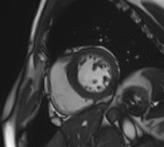

心脏